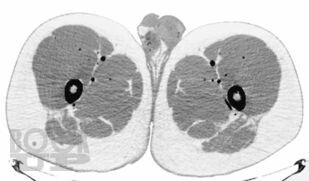

В руководстве подробно описана методология проведения компьютерно-томографического исследования при эндокринологических заболеваниях, рассмотрены основные диагностические аспекты и возможности компьютерной томографии при образованиях надпочечников, щитовидных и паращитовидных желез, гипофиза, заболеваниях костей и офтальмопатии. Продемонстрированы также возможности современной мультиспиральной компьютерной томографии в диагностике эндокринопатий. Издание иллюстрировано большим количеством компьютерных томограмм.